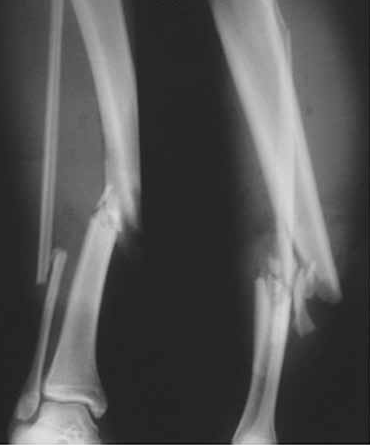

Após um acidente automobilístico um indivíduo sofreu fratura nos ossos da perna. Observe a radiografia abaixo, indicando a localização da fratura.

Adaptado de: Kojima, K. E.; Ferreira, R. V. Fraturas da diáfise da tíbia. Rev Bras Ortop. 2011;46(2):130-5

Em relação ao sistema esquelético e à fratura presente na imagem, analise as afirmativas a seguir: